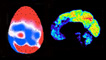

Neuroscientist's shocking brain scan results